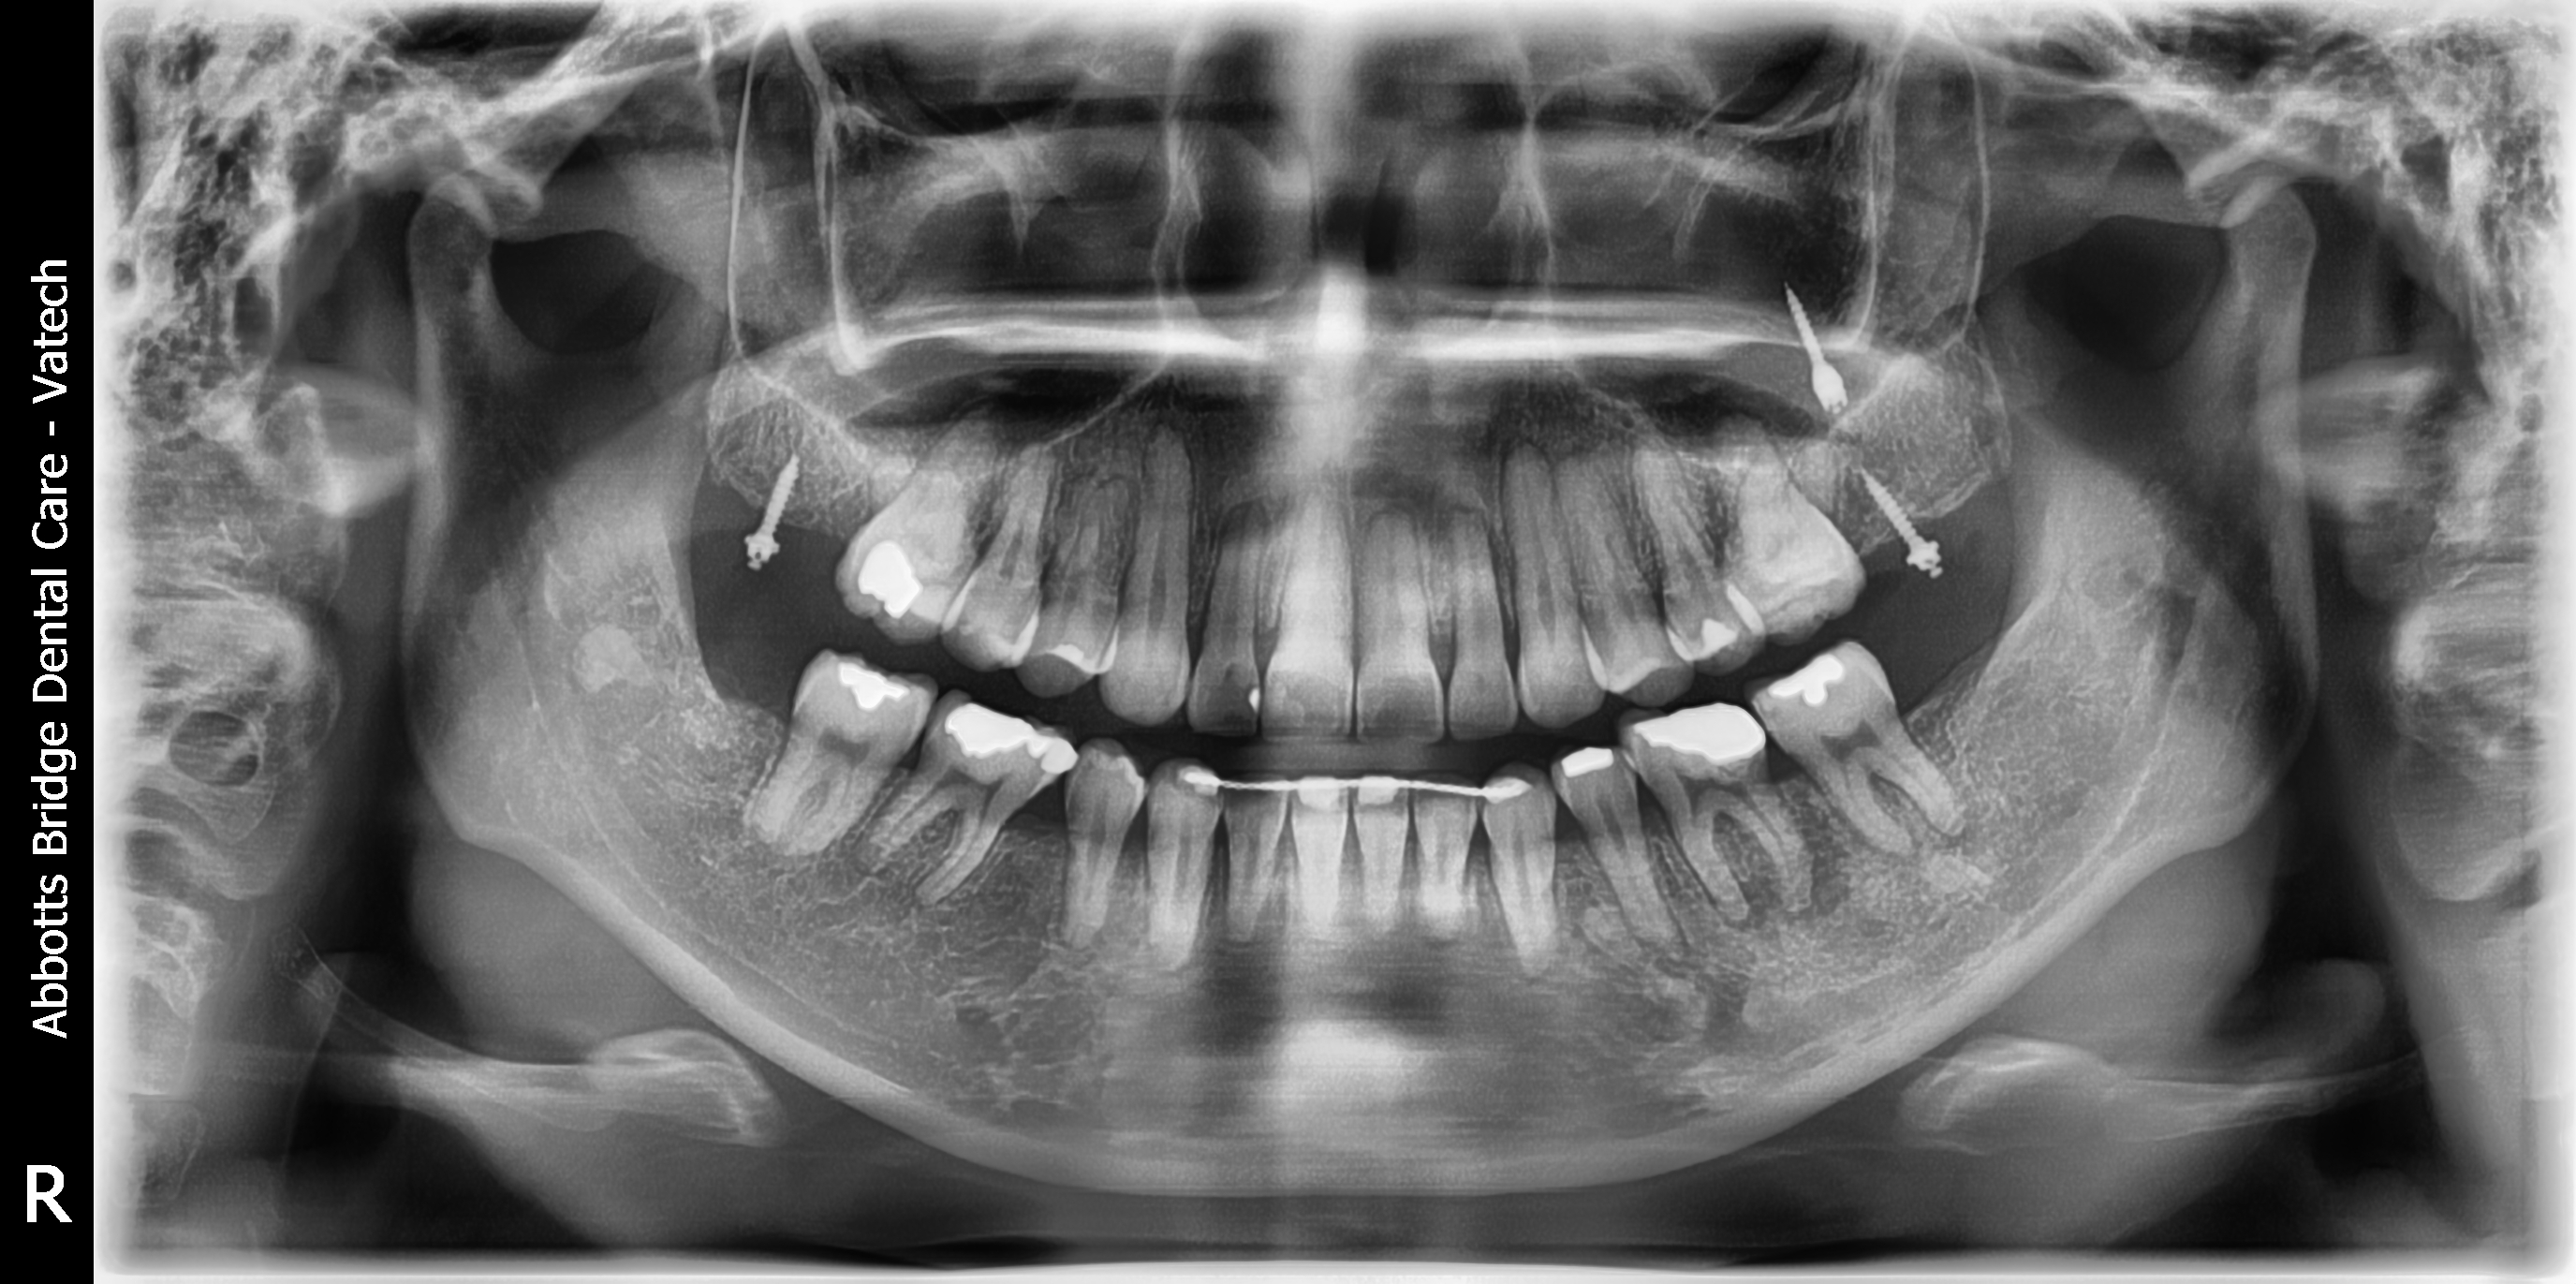

撤除矫正器即刻

Return to Webinar   Retention   Five-Month Post Debanding  植牙,导板与正畸

Xin Wei, DDS, PhD, MS 1st edition 01/11/2018, last revision 01/10/2021